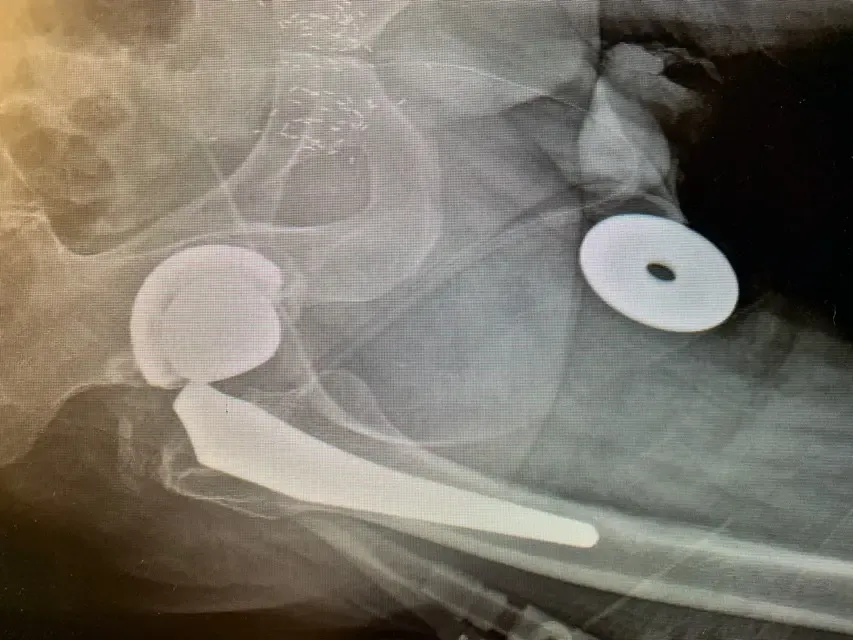

Las radiografías de película simple revelaron adelgazamiento y «lápiz» del cuello del componente femoral, lo que indica probable corrosión por los trastes en el trunion, también conocida como «trunnionosis».

De hecho, las radiografías sugerían que la unión se había corroído tanto que se había fracturado. Una investigación más profunda reveló que el tipo de componente utilizado en la cirugía de reemplazo inicial ha demostrado desde entonces sufrir este fenómeno a un ritmo más alto que otros, aunque esto no se sabía en ese momento.